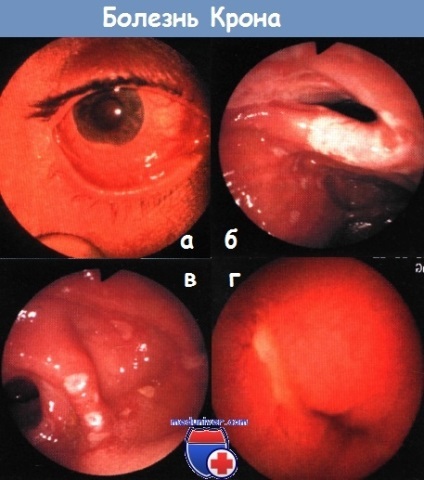

b - boala lui Crohn: stomatita aftoasa

In boala Crohn a intestinului subțire examinat în principal metoda radiografice. În unele cazuri, acesta este înlocuit cu o colonoscopie, care permite de a inspecta mucoasa ileonului, și enteroscopy orală, care a început să folosească recent. scopuri de diagnosticare sunt de a utiliza capsula endoscopie, dar este întotdeauna riscul ca capsula devine blocat pe stricturi colon, a căror prezență nu este suspectat.

b - ileita terminală boala lui Crohn. Ileoskopiya colonoscopie.

in - o recidivă a bolii Crohn după rezecție: a lovit restul segmentului terminal al ileonului.

r - ulcere în jejun în boala Crohn. Capsule endoscopie.